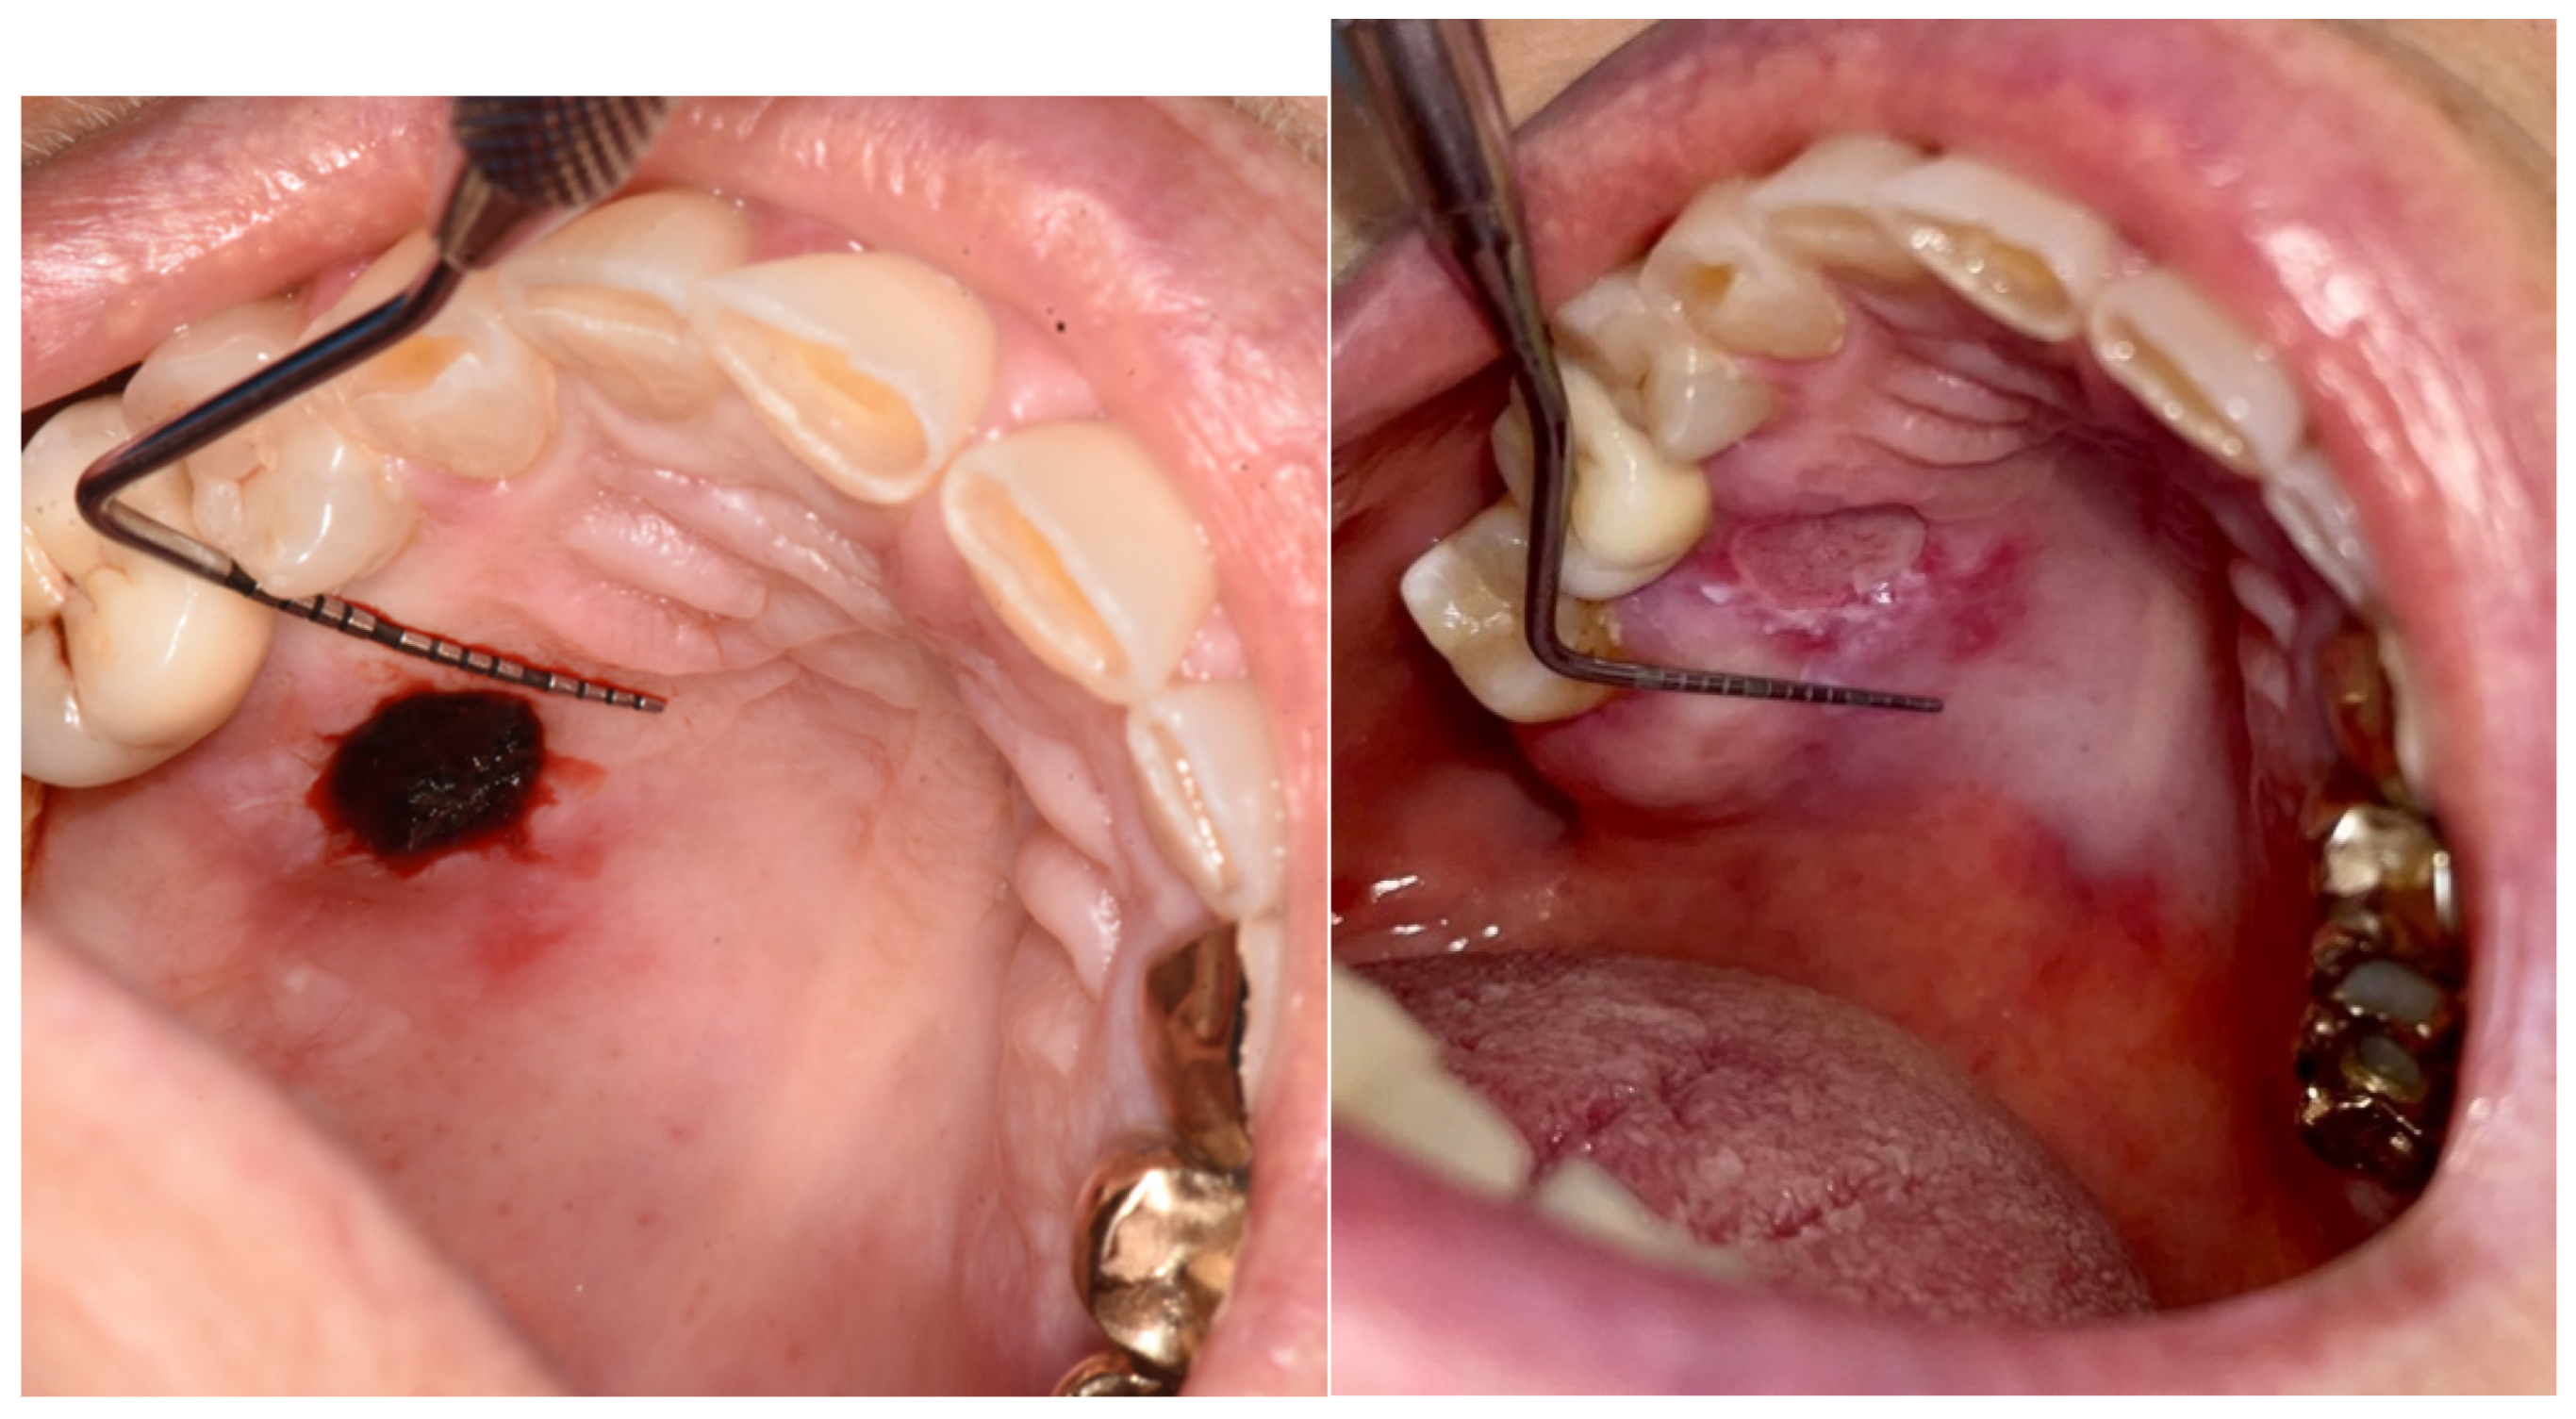

Figure 5. A biopsy in the loose mucosa (buccal mucosa) in the immediately post-op and at day 6.